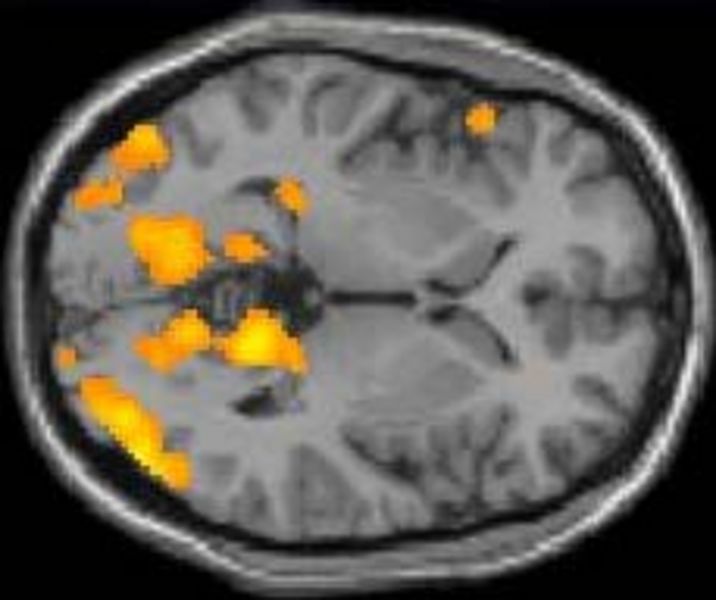

Die Arbeitsgruppe "Cognition & Gender" sucht regelmäßig gesunde Probandinnen und Probanden für Forschungsprojekte mit funktioneller Magnetresonanztomographie (fMRT) am Universitätsklinikum Münster (UKM).